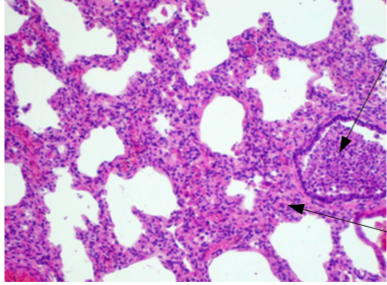

Identify Lesion

What is the cause?

Bronchopneumonia

Caused by infection of air way (trachea, bronchi)

Streptococci, staphylococci